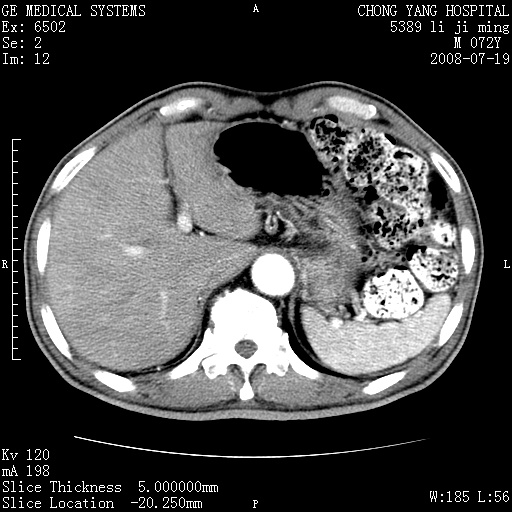

以下是引用zjzjr在2008-7-19 20:57:00的发言:[br]胰头增大,边缘模糊,周围可见渗出影,右侧肾前筋膜增厚.支持胰腺炎.

以下是引用yangyudong333在2008-7-20 6:56:00的发言:[br]胰腺增大尤以胰头明显,边缘模糊,周围可见渗出影,右侧肾前筋膜增厚,肠管於涨.支持胰腺炎

以下是引用不学无术在2008-7-19 23:15:00的发言:[br]胰腺增大尤以胰头明显,边缘模糊,周围可见渗出影,右侧肾前筋膜增厚,肠管於涨.支持胰腺炎